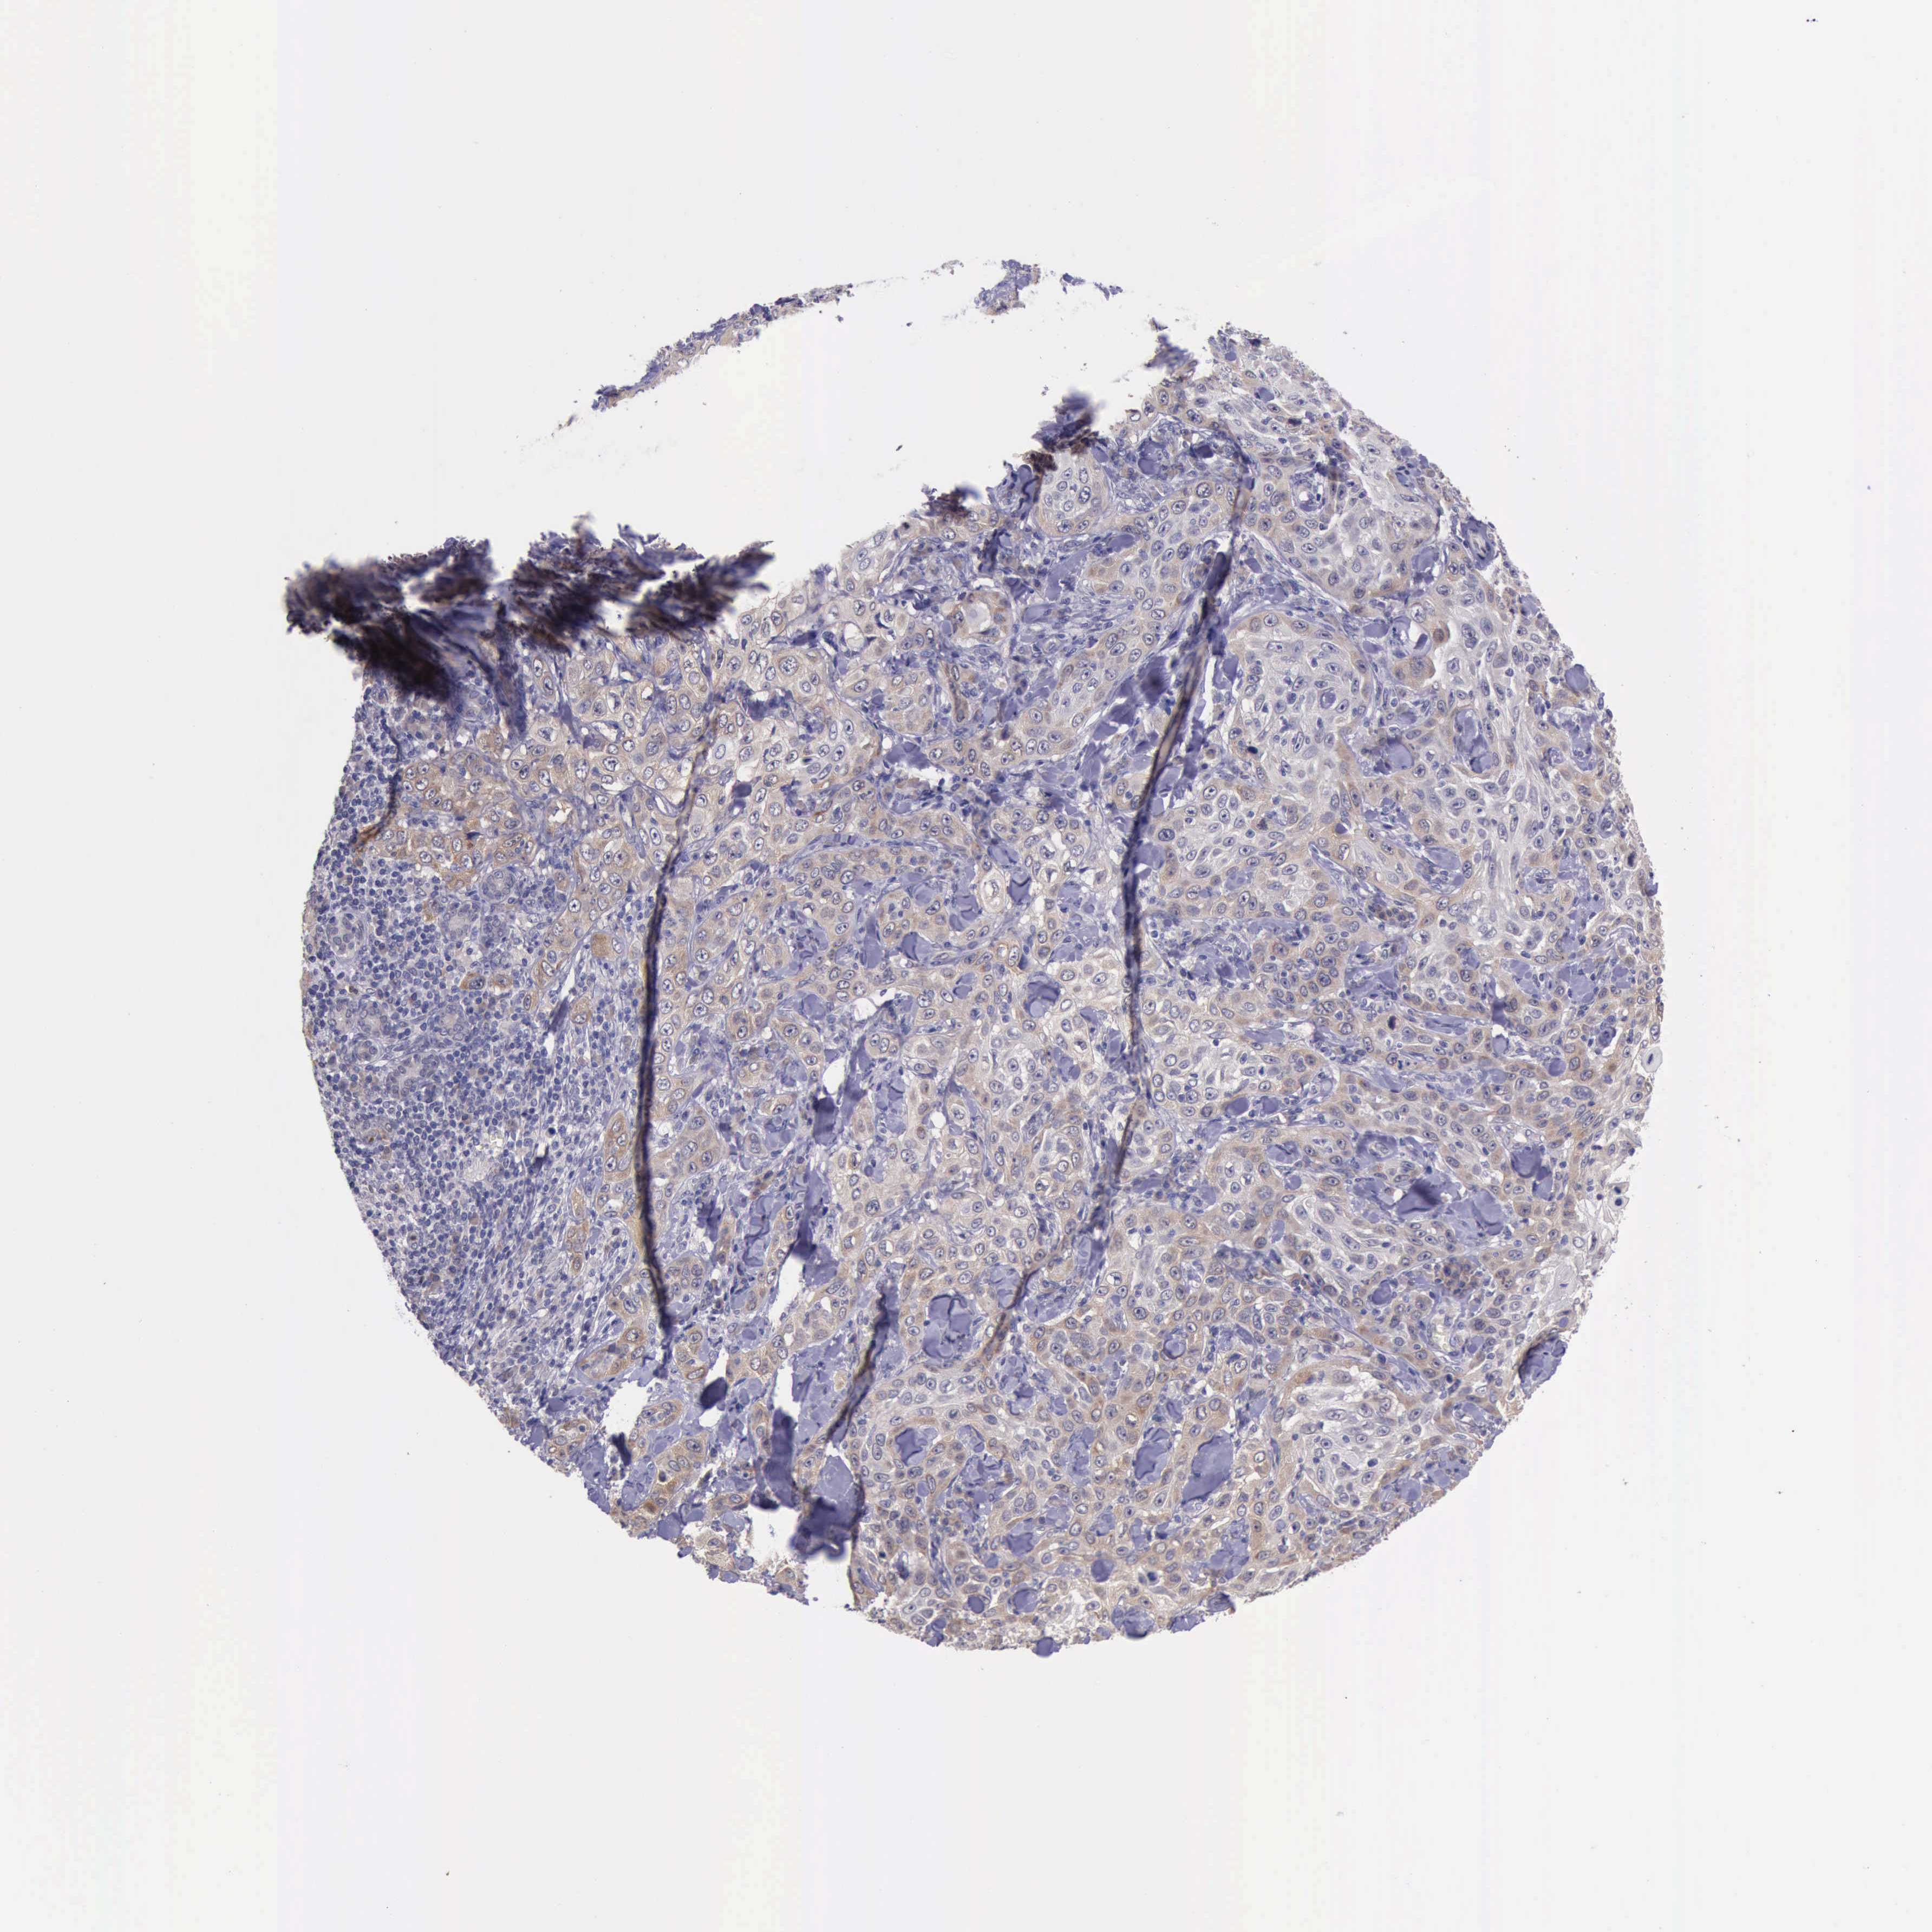

SKIN CANCER - Protein expressioni

A mouse-over function shows sample information and annotation data. Click on an image to view it in a full screen mode. Samples can be filtered based on level of antibody staining by selecting one or several of the following categories: high, medium, low and not detected. The assay and annotation is described here.

Antibody staining in the annotated cell types in the current human tissue is reported as not detected, low, medium, or high, based on conventional immunohistochemistry profiling in selected tissues. This score is based on the combination of the staining intensity and fraction of stained cells.

Each image is clickable and will lead to virtual microscopy that enables deeper exploration of all samples and also displays staining intensity scores, fraction scores and subcellular localization as well as patient and tissue information for each sample.

Antibody HPA001208

Squamous cell carcinoma, NOS

Basal cell carcinoma